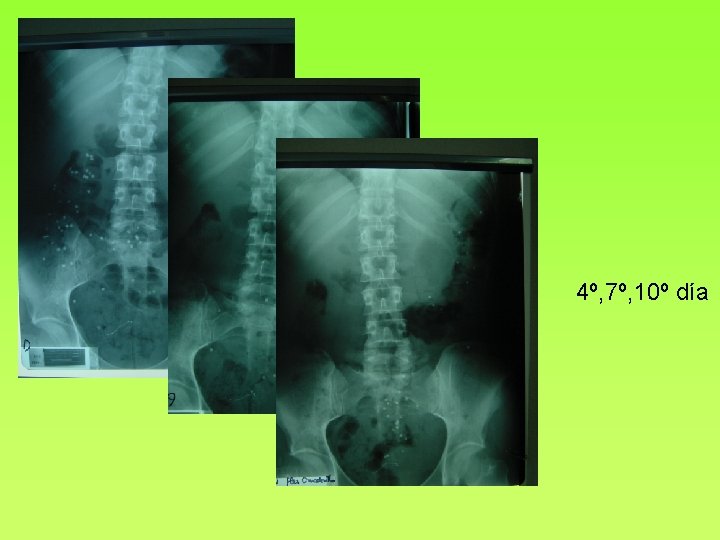

Posevacuación